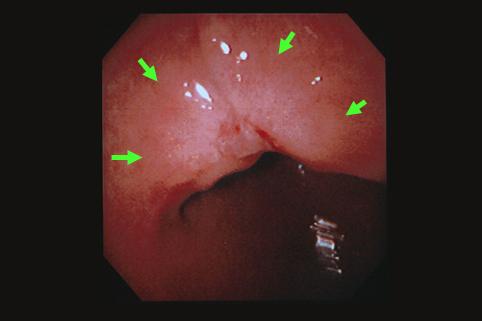

clasificación del pacienteTumor Epitelial Maligno/Adenocarcinoma

parte(separada por órganos)estómago(región)/ángulo

método de exámenEndoscopia

clasificación ectoscópica de tumoresTipo 0(tipo superficial)/Tipo IIc(IIc+III)

diámetro mayor del tumor25 - 29

grado de penetraciónm